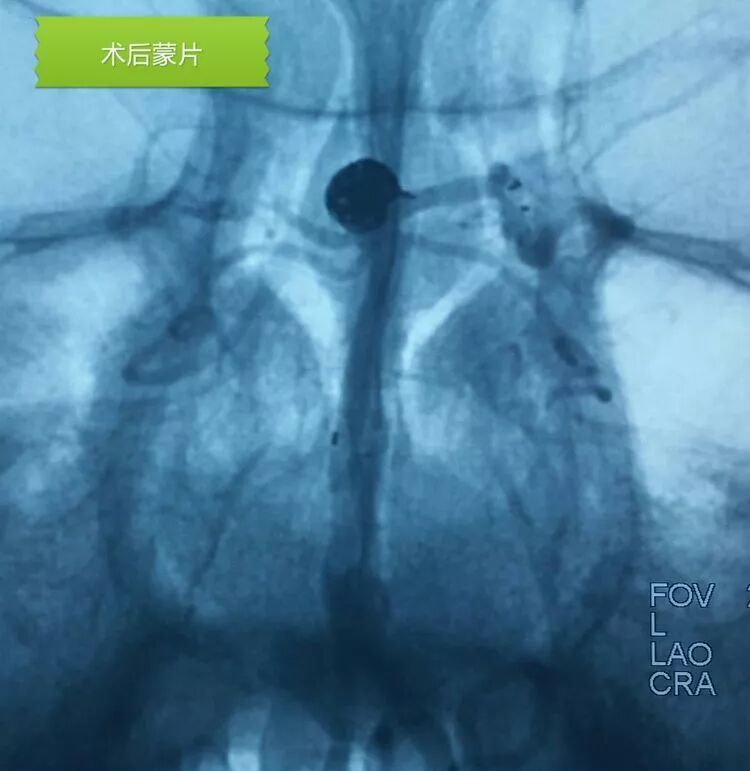

栓塞后的工作位造影和蒙片

应用Solitaire支架结合双微管栓塞,一根微导管是45°预塑形的,管头置于瘤体中央(浅管),另一根微导管管头塑成C形,沿瘤底深入到瘤体右侧角(深管)